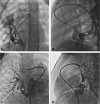

Methods: Between April 2011 and November 2018, 22 patients underwent scimitar vein surgery; 11 had baffling or reimplantation and 11 only had the new operation that included resection of the atrial septum with removal of the muscular limbus. The left atrium was pulled down toward the scimitar vein and a V-shaped incision made at the scimitar vein atrial junction with the space filled with a pulmonary homograft. If the scimitar vein coursed adjacent to the atrium, a V-shaped incision was made into the scimitar vein and directly anastomosed to the atrium. A patch of autologous pericardium was used to septate the atrium and an additional patch placed anteriorly to augment the inferior vena cava.